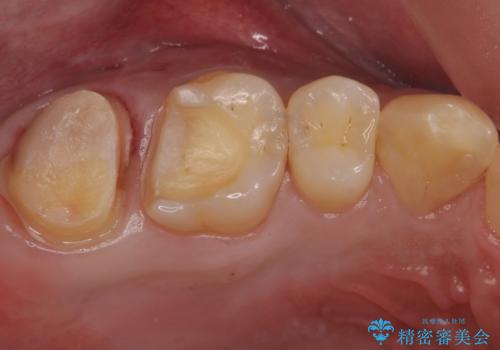

- 一番奥の銀の詰め物を白くしたいとのことで来院。

セラミックの詰め物のやりかえだと範囲が多く、割れてしまうリスクがあります。

そのため、割れるリスクが少ない詰め物ではなく、被せ物による治療(ジルコニアクラウン)を行いました。

また、隣の歯も白い樹脂の下が虫歯になっており、セラミックの詰め物(e-maxインレー)による修復をしました。